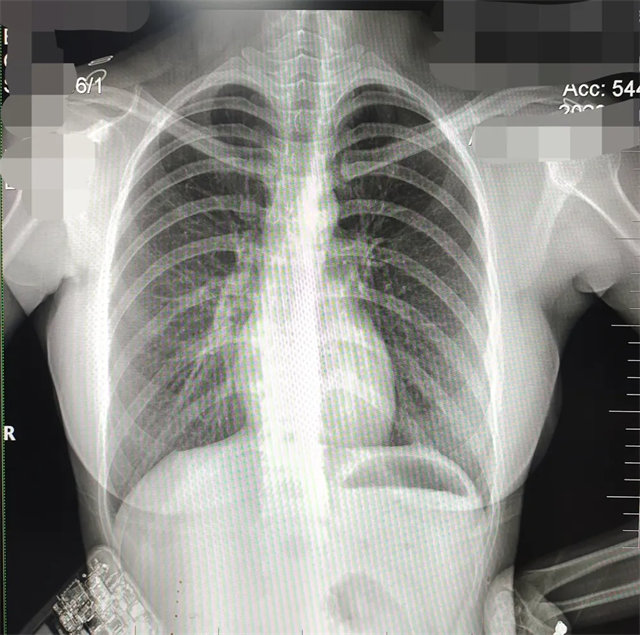

缺陷:雙側(cè)胸鎖關(guān)節(jié)不對稱,且有手機顯影。

解決:去除手機后,使患者左側(cè)緊貼成像件曝光。